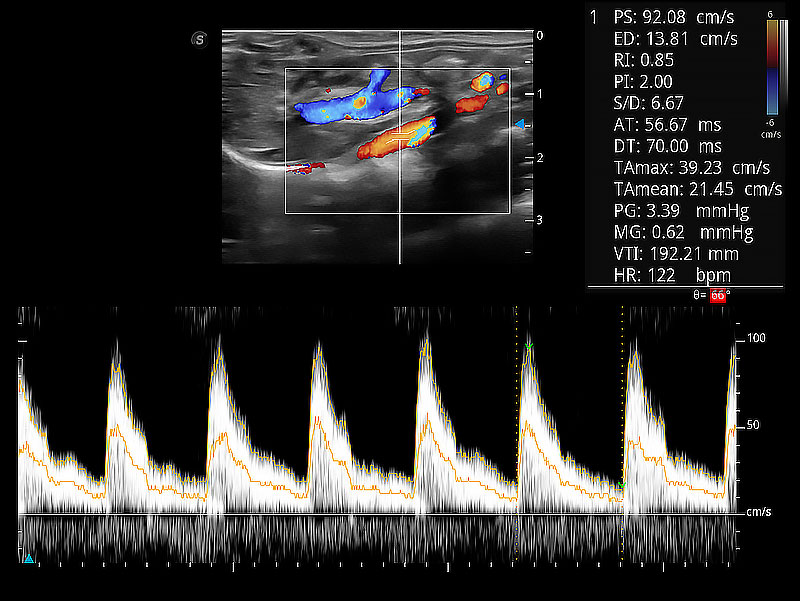

極大提升超低速微細血流的檢出能力,同時更精準地濾除軟組織和超聲信號,為獸用醫(yī)生提供以往無法通過常規(guī)血流獲得的疾病診斷信息。

隨著取樣門位置改變,頻譜多普勒包絡(luò)可進行自動眼蹤測量,且可自由配置測量的參數(shù)。